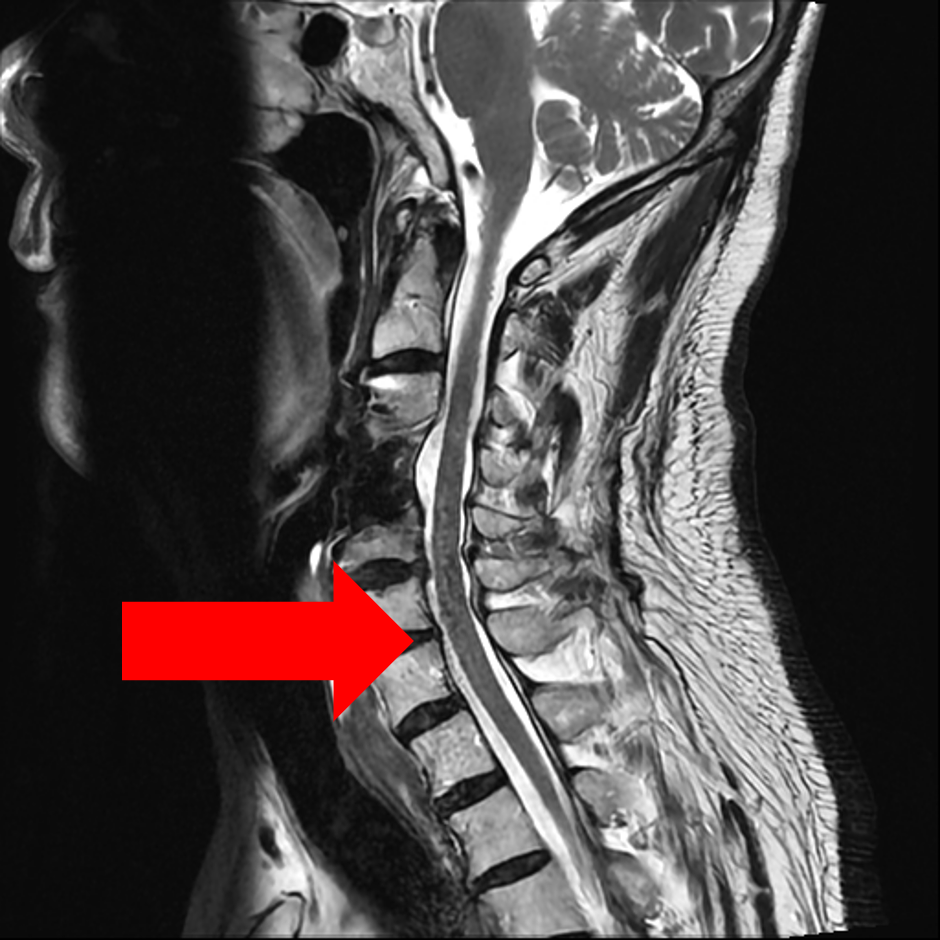

圖二、【術前評估】第五、第六頸椎椎間盤突出往後擠壓到脊髓腔(如左圖箭頭)、椎間盤突出往後偏右擠壓到第六條神經(如右圖箭頭)。

圖三、【術前評估】第六第七頸椎間盤突出往後擠壓到脊髓腔(如左圖箭頭)、同時顯示椎間盤突出往後偏右已擠壓到第七條神經(如右圖箭頭)。